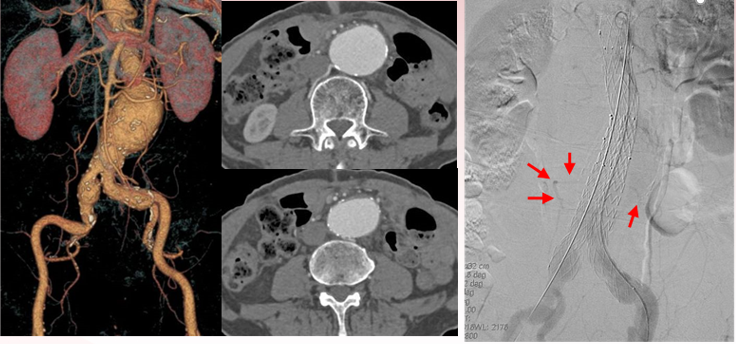

II型内漏 预防:预栓IMA

★ Case 2

II型内漏 预防:预栓腰A